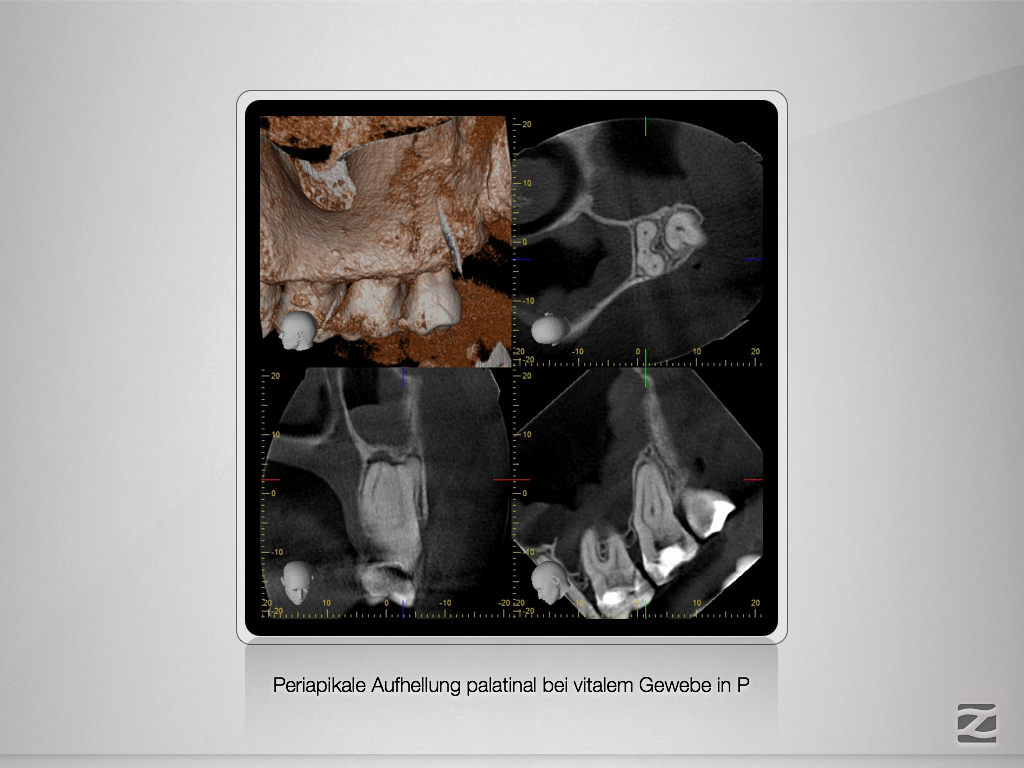

Vitales Gewebe – apikale Aufhellung